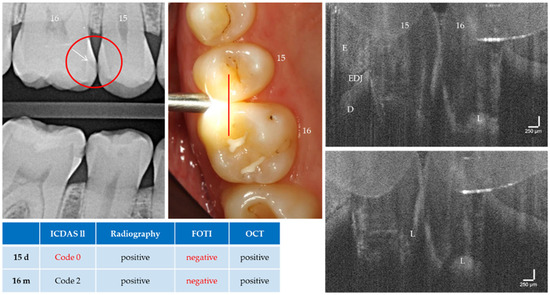

Figure 10.

Teeth 16 (m) and 15 (d). The OCT detects a cavitated carious dentin lesion (L) on tooth 16 mesially as a diagonal signal line (see Figure 5b). In contrast, the distal surface of tooth 15 appears demineralized and intact. Both lesions can be detected radiologically (arrow) but not with FOTI. Tooth 15 distal showed no visual evidence of a lesion. As a result of focusing on deeper structures, the tooth surface has flipped in the OCT images. Enamel (E), dentin (D), enamel-dentin junction (EDJ). The vertical scales are related to the refractive index n = 1.0 (see remark in Figure 4).